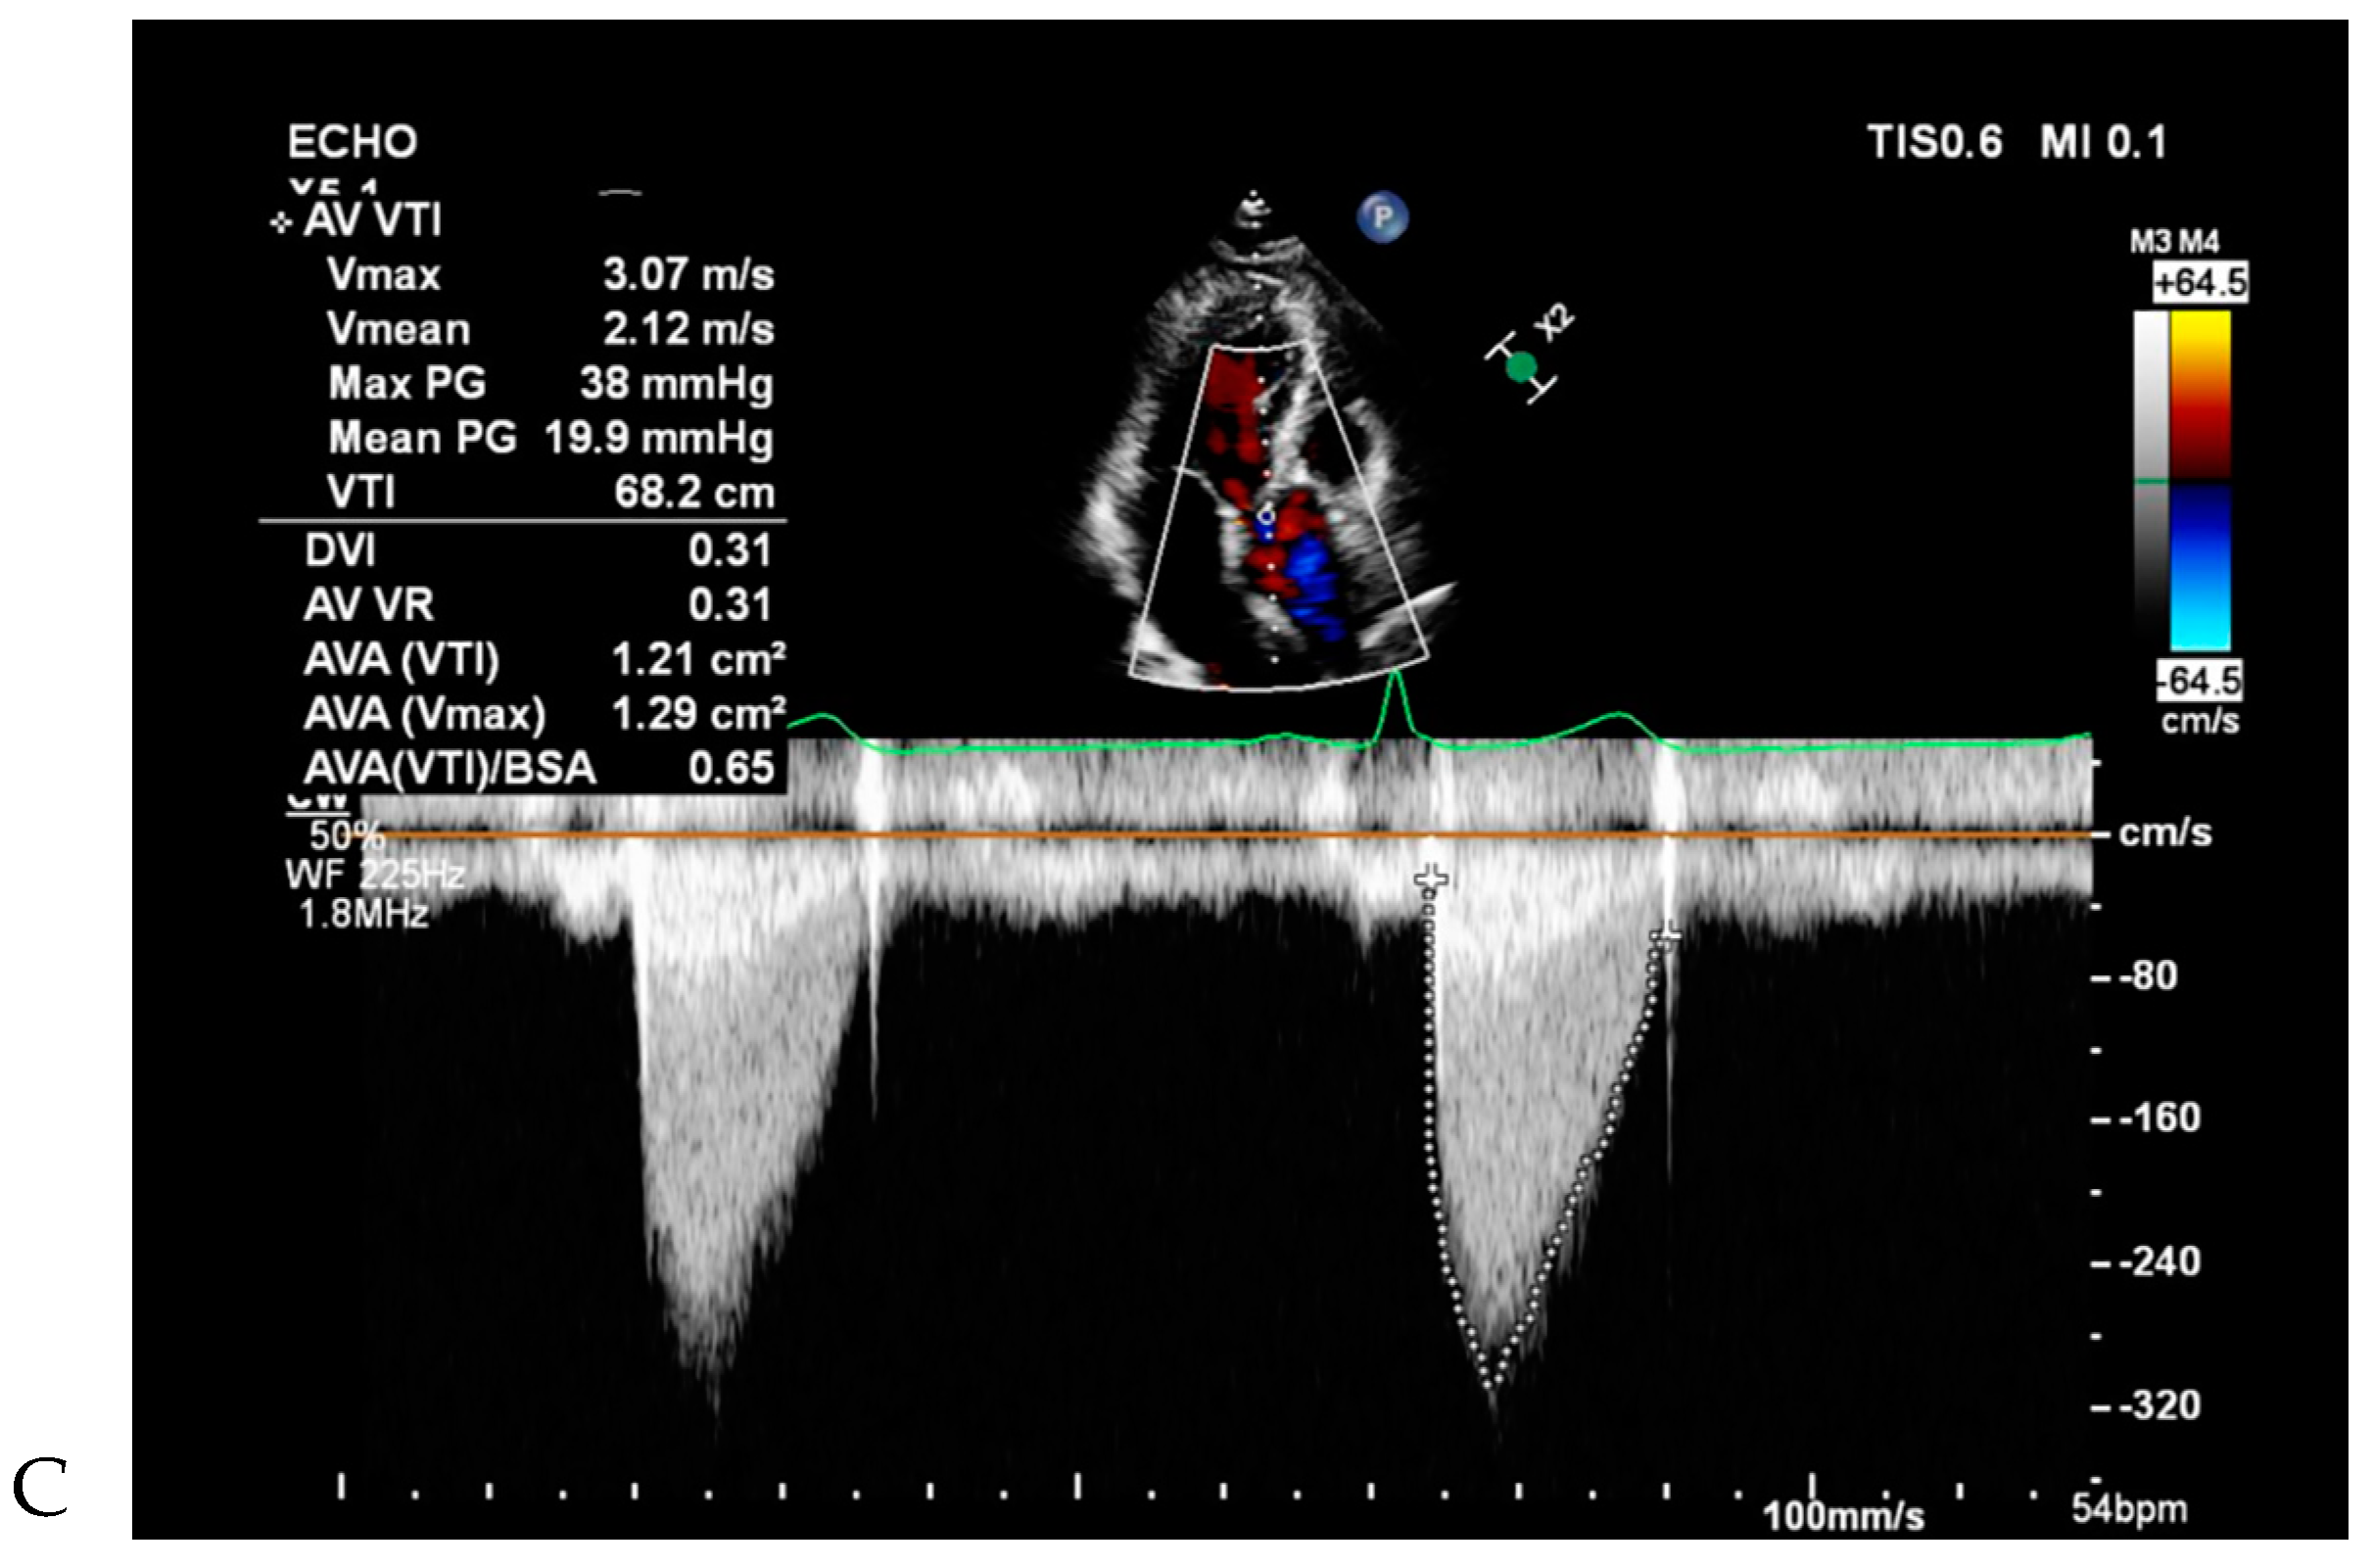

Figure 5. Bicuspid aortic valve (BAV) without raphe and combined aortic root as well as mid ascending aorta in a 64-year-old male. (A) Double oblique CT reconstruction parallel to the aortic valve demonstrates thickened, calcified BAV cusps without raphe. (B) Diameters of the sinuses of Valsalva 43.5 mm (size index 2.24 cm/m2) and mid ascending aorta 46.4 mm (size index 2.48 cm/m2), which were measured at mid-systole. (C) Continuous-wave Doppler recording of the aortic stenosis jet from an apical approach shows a maximum velocity of 3.07 m/sec. The continuity equation of the aortic valve area was 1.2 cm2, corresponding to moderate aortic stenosis.